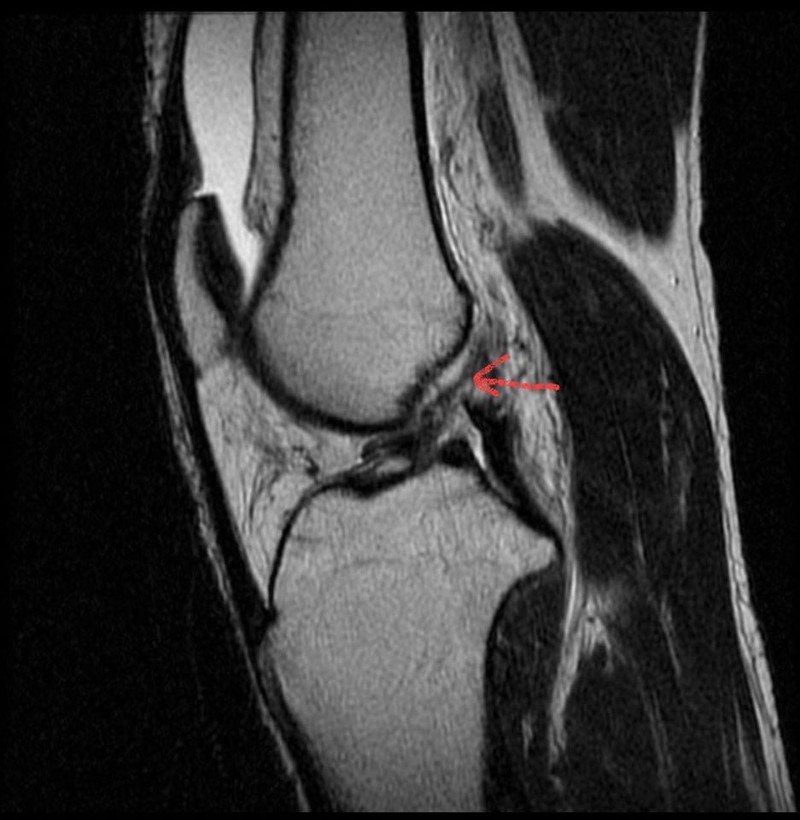

Qua thăm khám, các bác sĩ nhận thấy gối phải bệnh nhân lỏng, test Lachman, test ngăn kéo trước trên MRI phát hiện có hình ảnh đứt hoàn toàn dây chằng chéo trước khớp gối. Bệnh nhân được chẩn đoán đứt dây chằng chéo trước khớp gối và đã được phẫu thuật nội soi tái tạo dây chằng bằng phương pháp All Inside.

Hình ảnh đứt dây chằng chéo trước của bệnh nhân trên phim MRI. Ảnh: BVCC